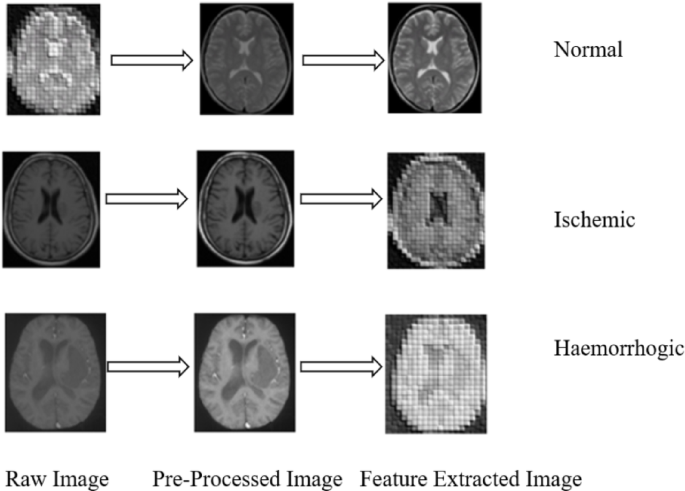

Experimental result of the proposed S3ET-NET. Each row illustrates the processing pipeline for a brain MRI image: the original input, the pre-processed image after Gaussian bilateral filtering, the extracted feature map using GhostNet, and the final classification result. The model accurately differentiates between Normal, Ischemic Stroke, and Hemorrhagic Stroke cases based on the extracted deep features.

The outcomes of the developed S3ET-NET are displayed in (Fig. 4). The patient’s MRI images have been considered as input and passed to pre-processing. These pre-processed images can be given for the feature extraction phase. Finally, the classification output, such as normal, IS, and HS, can be done with extracted images.